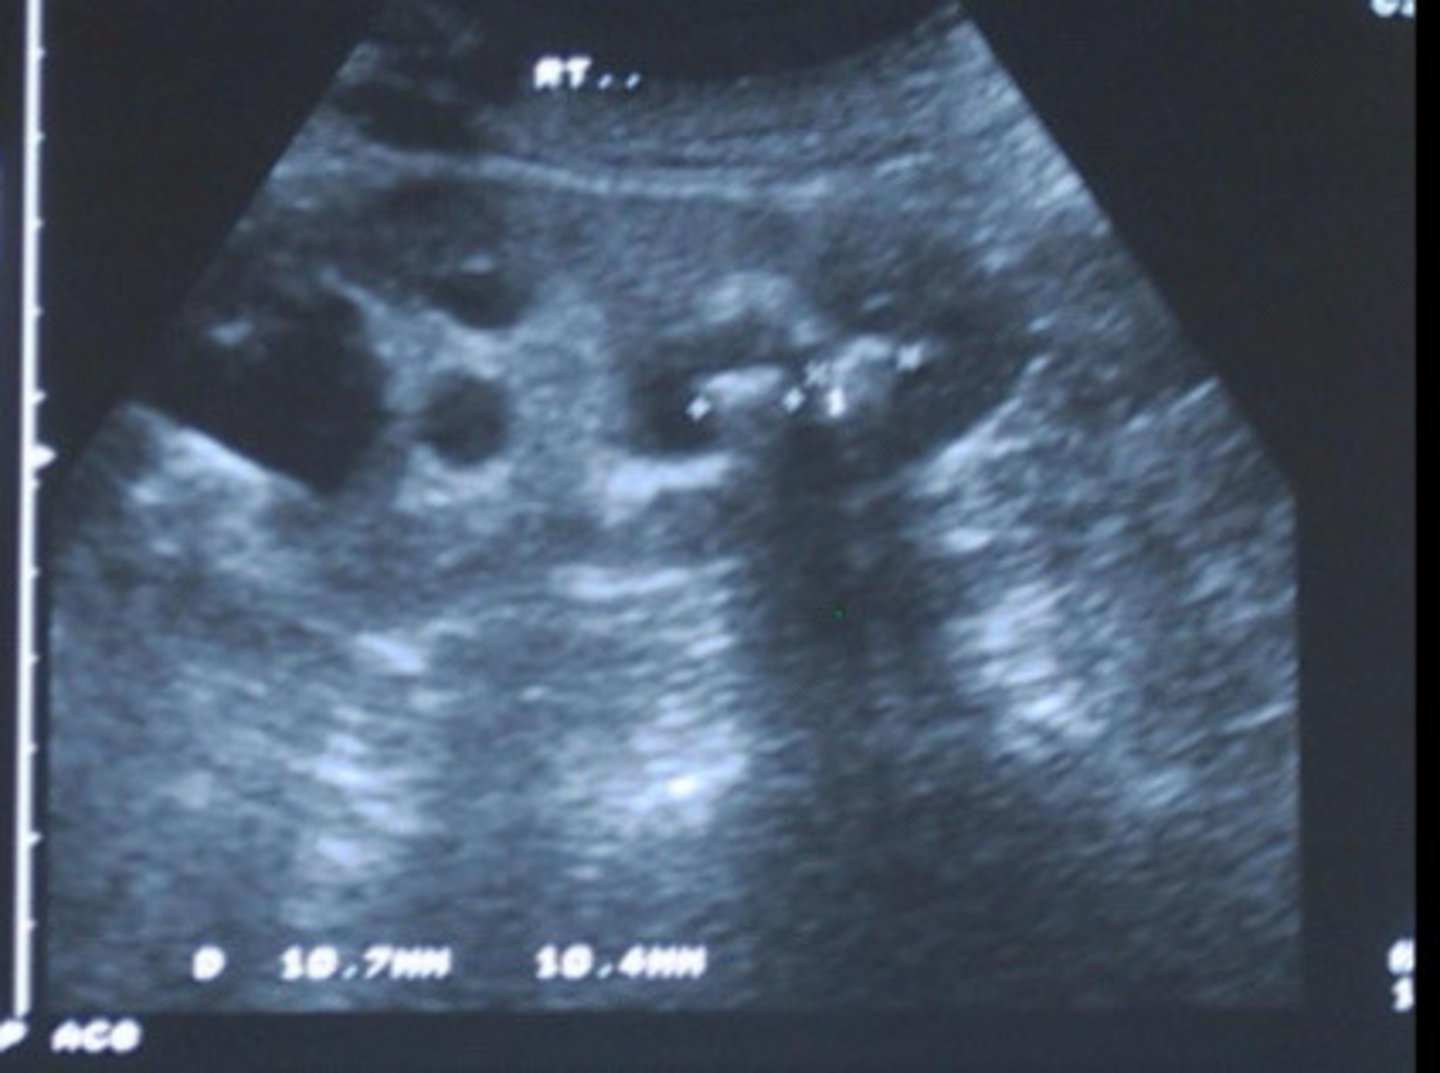

Grade 1 hydro

What does this image show

<p>What does this image show</p>